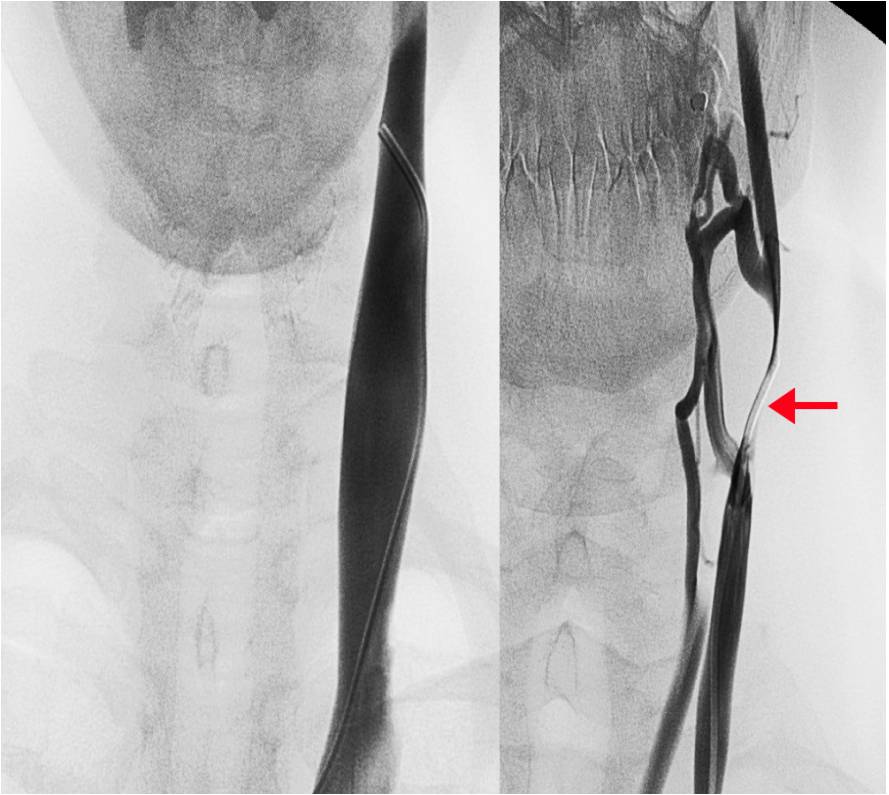

At 1 year follow up the EDSS was 3 again and the patient reported recurrent fatigue that she had been experiencing for several months. Further investigation revealed a CCSVI related left IJV tandem obstruction. At mid cervical level B-mode color Doppler demonstrated an IJV obstruction mirrored by an MRV imaging. In both cases a pencil tip pencil sign was demonstrated (Figure 2). The color Doppler assessment highlighted a left IJV dynamic flow obstacle caused by an extrinsic compression (Figure 2), that could be relieved by yawning.

At the caudal level a color Doppler detectable blocked outflow was demonstrated. The flow abnormality was linked to a M-mode evident fixed valve leaflet.

Considering a further PTA pointless, an open surgical access was placed. The macroscopic evidence of the extrinsic stricture, caused by a fibrotic and short OM intermediate tendon on the IJV, lead to the surgical transection of the two muscular bellies. In addition, endophlebectomy of the terminal IJV permitted the removal of a fibrotic septum. The procedure was completed by patch angioplasty by using an autologous great saphenous vein. The patient tolerated the procedure well and neither major nor minor complications were reported.

At 2 years follow up after the surgical operation, the color Doppler assessment detected a persistent and monodirectional physiologic IJV flow, which improved considerably from being absent pre-operatively to the post-procedural 300 ml/min. The a EDSS value remained 1 and the patient did not report any other multiple sclerosis like relapses.